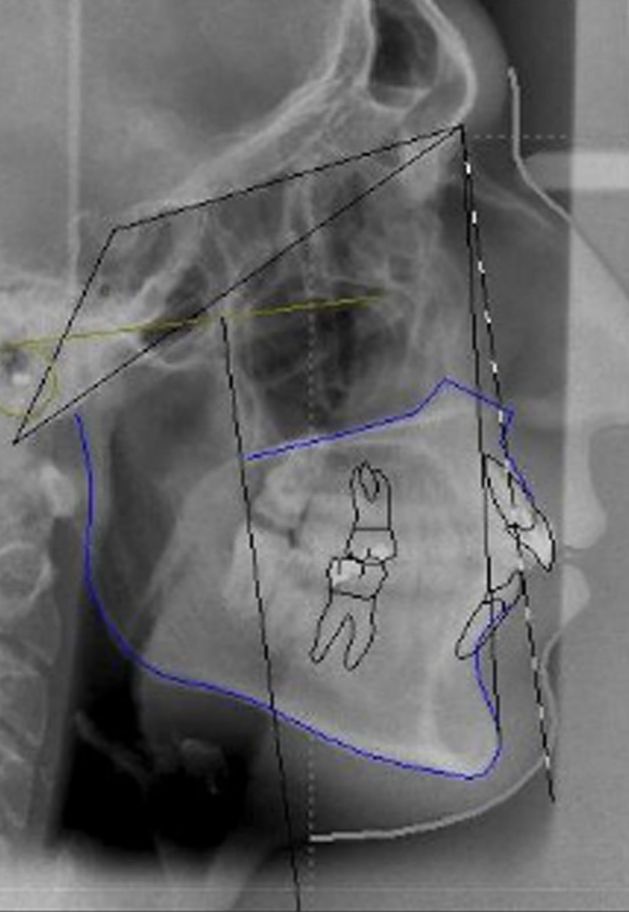

ΚΕΦΑΛΟΜΕΤΡΙΚΗ ΑΚΤΙΝΟΓΡΑΦΙΑ

Η ψηφιακή κεφαλομετρική αποτελεί μια ειδική πλάγια ακτινογραφία της κεφαλής που χρησιμοποιεί ο ορθοδοντικός για να επιλέξει το είδος της θεραπείας που θα ακολουθήσει. Η ακτινογραφία αυτή όμως έχει και άλλες ενδείξεις όπως στις περιπτώσεις υπερτροφίας των αδενοειδών εκβλαστήσεων (κρεατάκια) ή άλλων προβλημάτων του αεραγωγού.